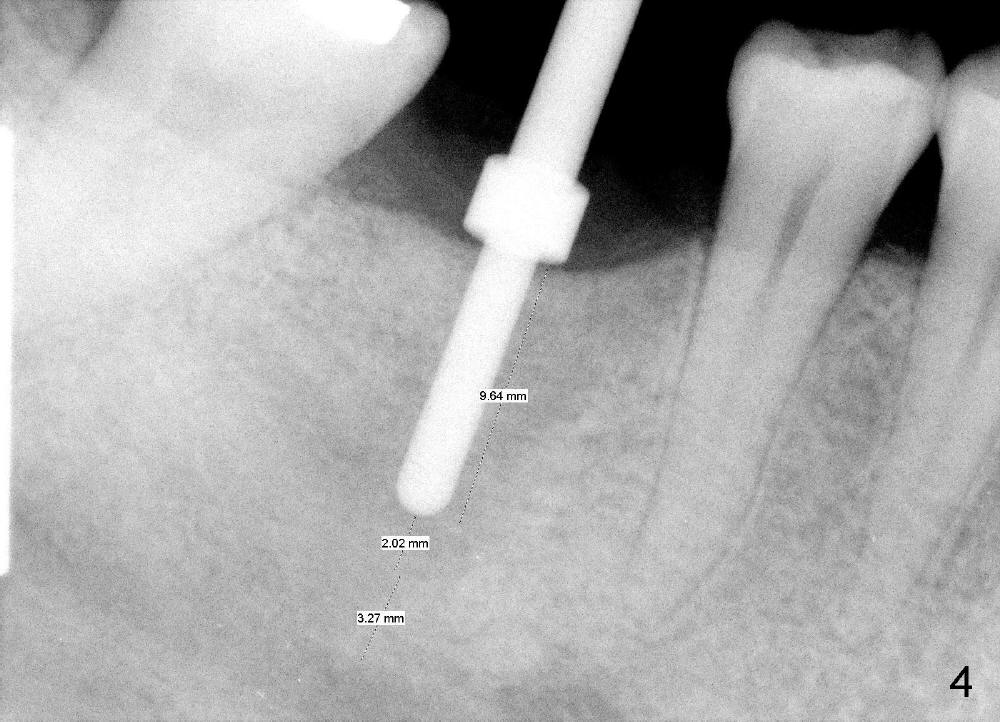

An incision is made instead of flapless, the socket is found to be filled with regenerated bone (Fig.3). After using 2 mm pilot drill, a paralleling pin is inserted to confirm trajectory and distance from the inferior alveolar nerve (Fig.4). Osteotomy is enlarged by Bicon reamers; threads are formed by insertion of Tatum 5x14 mm tap at the depth of 11 mm (Fig.5). The threads are visible when the tap is removed (Fig.6 ^). The advantage of using tap(s) is to test binding to the bone. If the tap is loose, the next sized tap should be used before placing a proper sized implant. This step is particularly critical when placing a large immediate implant or when the socket is immature.